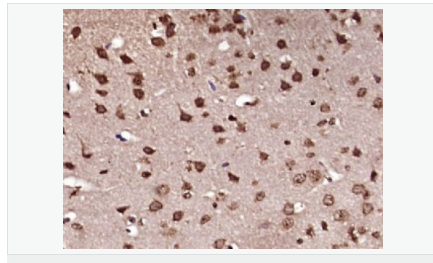

| 英文名稱 | Ferritin Heavy Chain/FTH1 |

| 中文名稱 | 鐵蛋白抗體 |

| 研究領域 | 心血管 細胞生物 免疫學 神經生物學 |

| 產品應用 | ELISA=1:5000-10000 IHC-P=1:100-500 IHC-F=1:100-500 Flow-Cyt=1ug/Test (石蠟切片需做抗原修復) not yet tested in other applications. optimal dilutions/concentrations should be determined by the end user. |

| 產品介紹 | This gene encodes the heavy subunit of ferritin, the major intracellular iron storage protein in prokaryotes and eukaryotes. It is composed of 24 subunits of the heavy and light ferritin chains. Variation in ferritin subunit composition may affect the rates of iron uptake and release in different tissues. A major function of ferritin is the storage of iron in a soluble and nontoxic state. Defects in ferritin proteins are associated with several neurodegenerative diseases. This gene has multiple pseudogenes. Several alternatively spliced transcript variants have been observed, but their biological validity has not been determined. [provided by RefSeq, Jul 2008]. Function: Stores iron in a soluble, non-toxic, readily available form. Important for iron homeostasis. Has ferroxidase activity. Iron is taken up in the ferrous form and deposited as ferric hydroxides after oxidation. Also plays a role in delivery of iron to cells. Mediates iron uptake in capsule cells of the developing kidney. Subunit: Oligomer of 24 subunits. There are two types of subunits: L (light) chain and H (heavy) chain. The major chain can be light or heavy, depending on the species and tissue type. The functional molecule forms a roughly spherical shell with a diameter of 12 nm and contains a central cavity into which the insoluble mineral iron core is deposited. Subcellular Location: Cytoplasmic. Tissue Specificity: In human liver the heavy chain is the major chain. Similarity: Belongs to the ferritin family. Contains 1 ferritin-like diiron domain. SWISS: P02794 Gene ID: 2495 Database links: Entrez Gene: 2495 Human Entrez Gene: 14319 Mouse Entrez Gene: 100173063 Orangutan Omim: 134770 Human SwissProt: P02794 Human SwissProt: P09528 Mouse SwissProt: Q5R8J7 Orangutan Unigene: 524910 Human Unigene: 645560 Human Unigene: 1776 Mouse Important Note: This product as supplied is intended for research use only, not for use in human, therapeutic or diagnostic applications. |